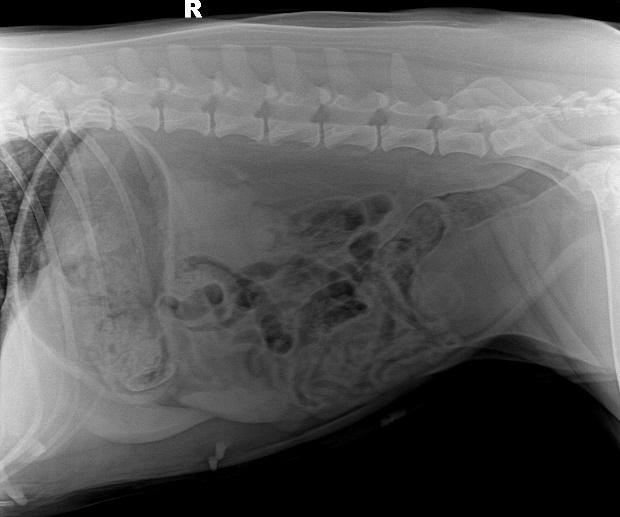

b. X射线检查:对于阻线性较强的物质(如金属、骨头)较容易辨别,对于阻线性与组织密度相似的物体较难确定,但是可以通过消化道灌服造影剂判断是否有阻塞或可包裹物体。

胃的正常大小:胃位于前腹部,隔和胆脏之后。胃排空时位于肋弓以内;从腹底算起,胃的腹侧缘大约在腹腔深度的1/3处。胃充盈时,胃向后向下延伸,与横结肠和腹底部相接。

摆位对

胃内异物(金毛,手术取出6cm大衣扣子)

钡餐4小时后胃内未排空(家猫,线性异物)